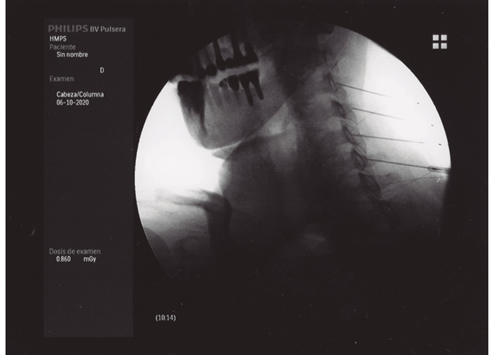

Figura 2